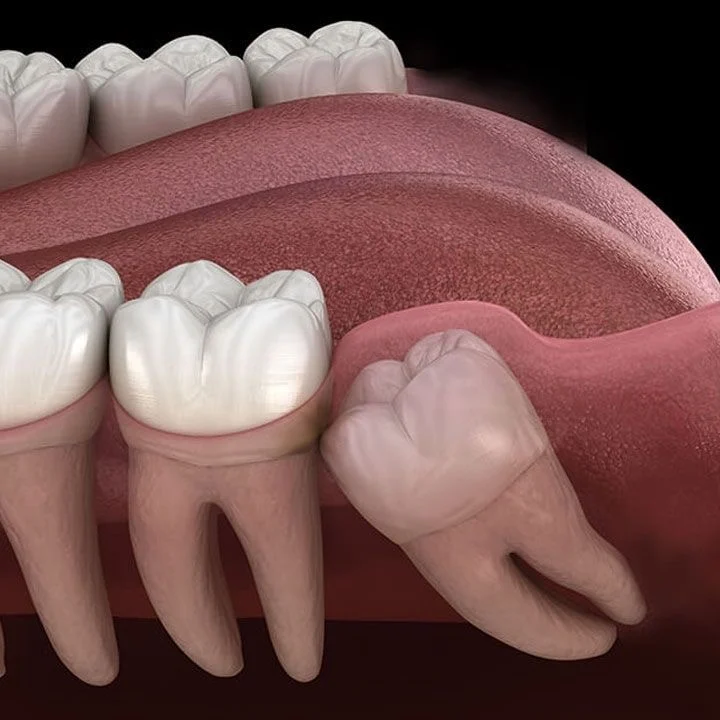

Vadjenje umnjaka

Umnjak može izazivati tegobe u vidu bola,otežanog otvaranja usta,ugrožavanje susednog zuba i dr.

Bezbolna ekstrakcija u lokalnoj anesteziji omogućava efikasno eliminisanje subjektivnih tegoba.